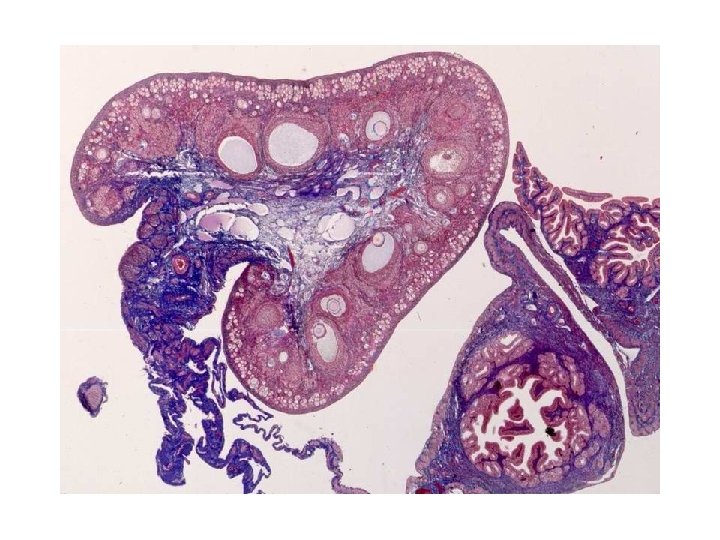

Ovarian Follicles ã Ovarian follicles located in cortex and surrounded by stromal cells ã A follicle consists of an oocyte surrounded by one or more layers of follicular cells ã 2 ovaries of young adult female have about 400, 000 follicles; most of them will degenerate (atresia) ã About 450 follicles will cycle to ovulation in lifetime

Types of Ovarian Follicles ü According to morphological characteristic follicles can be categorized into: ÖPrimordial Follicles ÖGrowing Follicles ÖUnilaminar primary follicles ÖMultilaminar primary follicles ÖSecondary follicles ÖMature Follicles (Tertiary or Graafian Follicles)

Primordial Follicle • Primordial follicles contain a primary oocyte that entered the prophase of first mitotic division • Primary oocyte surrounded with one layer of flattened follicular cells which are separated by a basal lamina from the stroma • Many of them degenerate during lifetime • Most numerous in fetus (several million) • One million at birth • At the onset of the buberty their number reduced to about a quarter of a million • Oocyte about 25 µm diameter • Euchromatic nucleus, large nucleolus

Growing Follicles ÔOocyte diameter increases to 100 to 150 µm ÔNucleus enlarges and called germinal vesicle(GV) ÔOrganelles increase in number and amount (mitochondria, several golgi complexes, RER, free ribosomes) ÔFollicular cells become cuboidal ÔUnilaminar primary follicle has one layer of cuboidal follicular cells ÔMultilaminar primary follicle has several layers of follicular (granulosa) cells

Secondary Follicles Ü Granulosa and theca cells increase in number Ü Fluid-filled spaces in granulosa layer fuse to form the antrum that become filled with liquor folliculi Ü This fluid is an exudates of plasma and produced by granulosa cells. It contains GAGs, proteoglycans, steroid binding protein, steroids and some hormones. Ü Cumulus oophorus is a small group of granulosa cells that surround primary oocyte and project into antrum Ü A single layer of granulosa cells that immediately surround the primary oocyte is known as corona radiata Ü Most of follicle at this stage become atretic Ü Some granulosa cells of atretic follicles do not degenerate and form interstitial glands which secret androgens

Mature (Graafian) Follicles ° Mature follicle develops due to continued proliferation of granulosa cells and production of more liquor folliculi which undergo ovulation ° By the time of ovulation it may be over 2. 5 cm in diameter ° Bulge from ovary surface ° Because of continued formation of liquor folliculi cumulus oophorus detaches and float freely in liquor folliculi